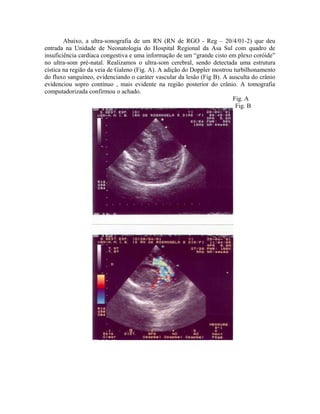

Abaixo, a ultra-sonografia de um RN (RN de RGO - Reg – 20/4/01-2) que deu

entrada na Unidade de Neonatologia do Hospital Regional da Asa Sul com quadro de

insuficiência cardíaca congestiva e uma informação de um “grande cisto em plexo coróide”

no ultra-som pré-natal. Realizamos o ultra-som cerebral, sendo detectada uma estrutura

cística na região da veia de Galeno (Fig. A). A adição do Doppler mostrou turbilhonamento

do fluxo sanguíneo, evidenciando o caráter vascular da lesão (Fig B). A ausculta do crânio

evidenciou sopro contínuo , mais evidente na região posterior do crânio. A tomografia

computadorizada confirmou o achado.

Fig. A

Fig. B